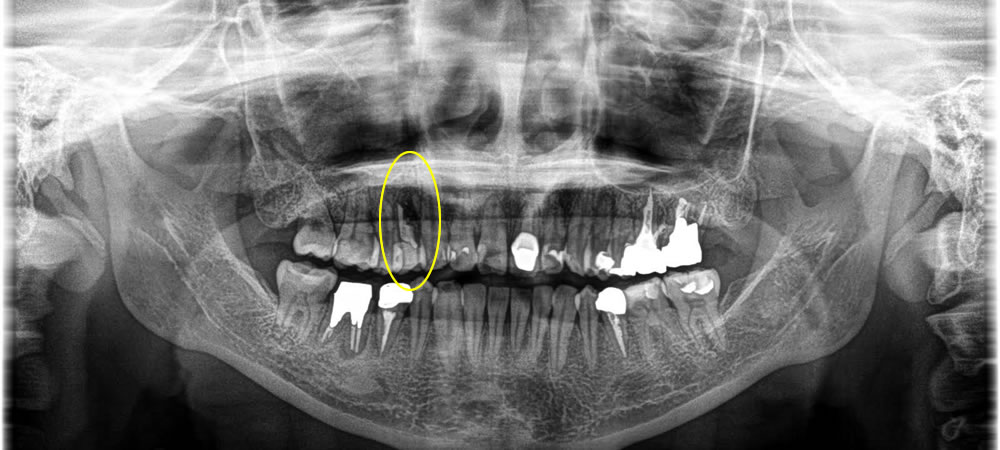

歯根破折した歯を抜歯後にインプラントで治療した症例

年齢

50代

性別

男性

症例を見る